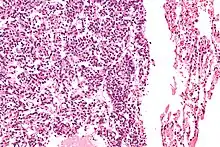

Micrograph of a typical pulmonary carcinoid tumour.

The definitive diagnosis is rendered by a microscopic examination, after excision. Typical carcinoids have cells with stippled chromatin and a moderate quantity of cytoplasm. They typically have few mitoses and lack necrosis. By definition, they are greater than 4 mm in largest dimension; smaller lesions are referred to as pulmonary carcinoid tumourlets.